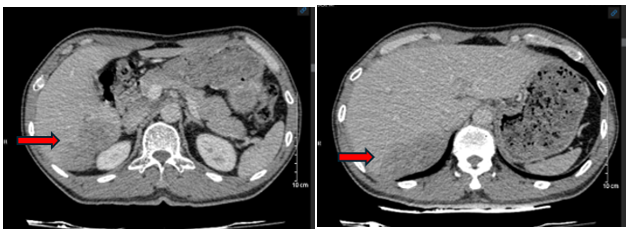

Hình ảnh Cắt lớp vi tính ổ bụng sau điều trị 01 tháng:

Hình 3: Nhu mô phân thùy sau gan phải sát bao gan có khối kích thước 54x67 mm, giảm tỉ trọng trước tiêm, sau tiêm ngấm thuốc kém hơn nhu mô gan lân cận, không thấy tăng sinh mạch (mũi tên đỏ)

Hình ảnh Cộng hưởng ổ bụng sau điều trị 03 tháng:

Hình 4: Hình ảnh khối u gan phải hiện không thấy tăng sinh mạch

Nhận xét: Sau 3 tháng điều trị, kích thước khối u gan giảm đáng kể, không còn huyết khối tĩnh mạch cửa, chỉ số AFP giảm đáng kể (từ 382,4 ng/ml xuống còn 10,2 ng/ml) sau 3 tháng điều trị.